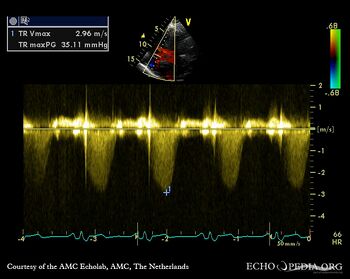

| Continuous-wave Doppler signal of moderate tricuspid regurgitation, peak gradient 35 mmHg